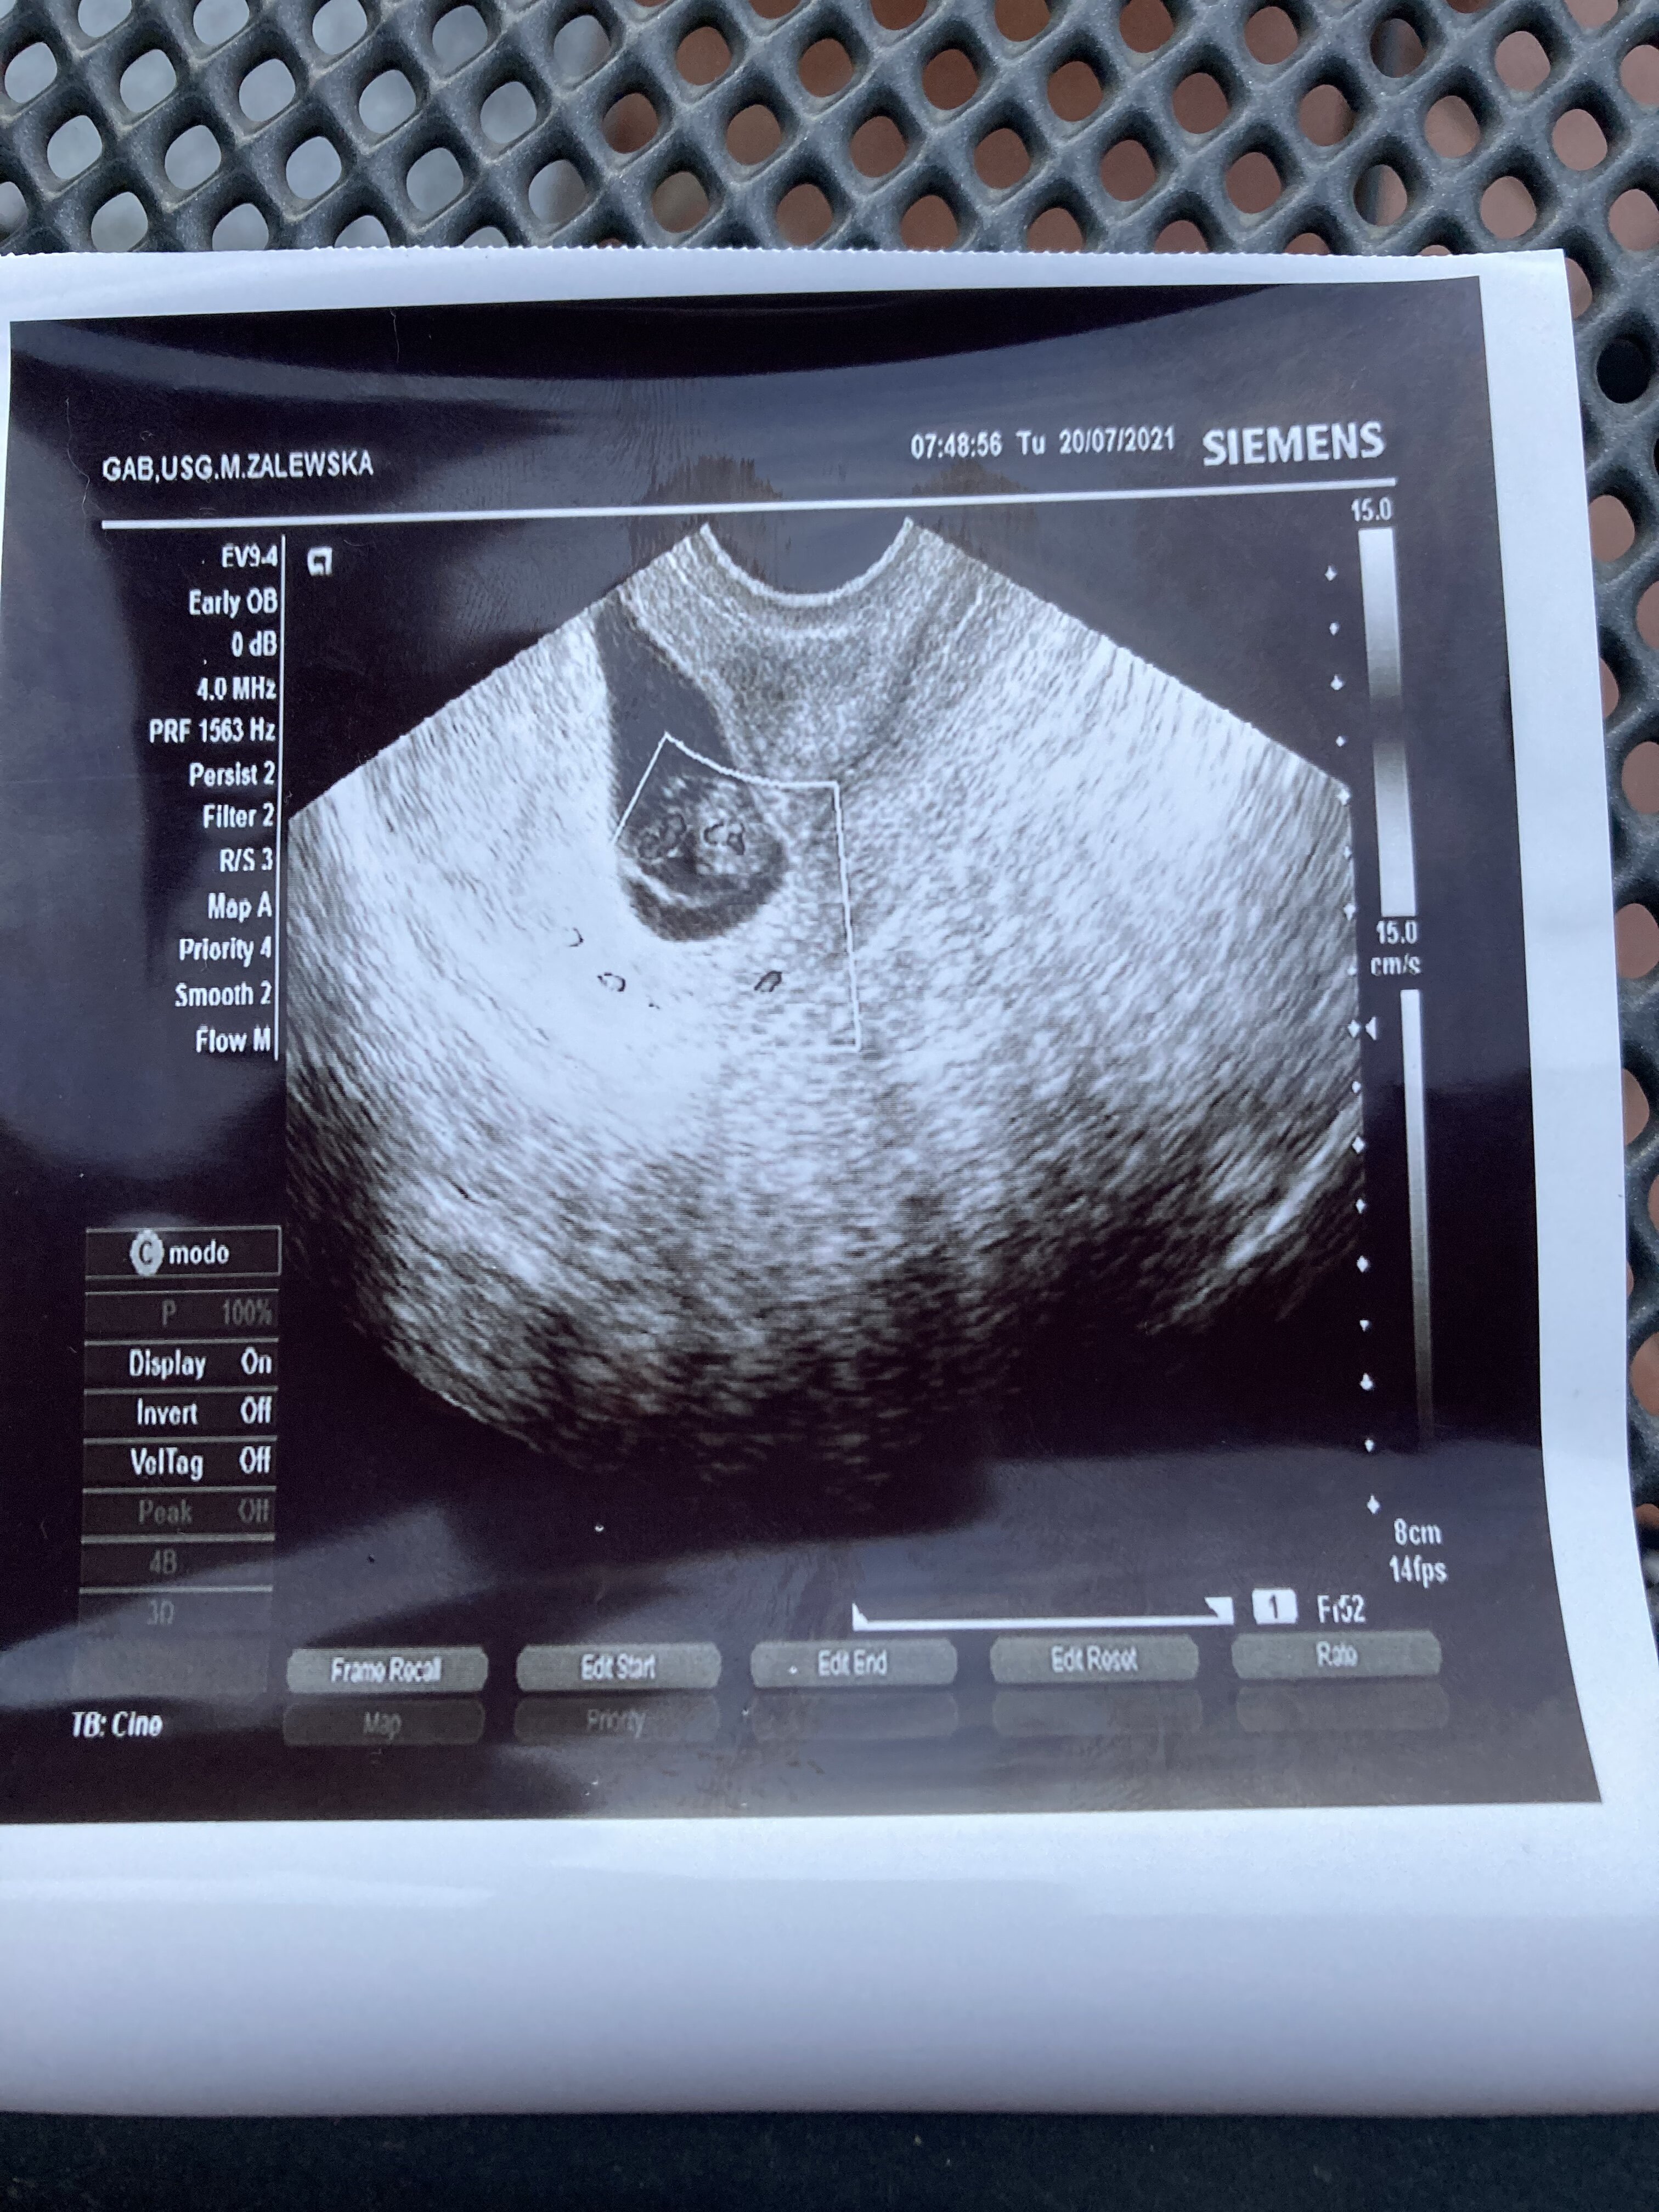

wszystko będzie dobrzeU mnie jest chyba nienajlepiej. Bliźniaki, ale jednojajowe. Lekarka powiedziała że od 20 tygodnia mogą się udusić i ze to w ogóle bardzo ciężka ciąża..

Zobacz załącznik 1296598